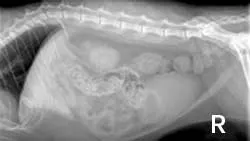

ImagingAbdominal radiographs showed small irregular kidneys (Figure 1, right: Radiograph of the right lateral abdomen. The kidneys are small and irregularly shaped. Mineral densities are visible in the left kidney. View larger image), and irregular margins were evident in ultrasound imaging (Figure 2, below: Ultrasound of the left kidney demonstrating irregular margins. View larger image).